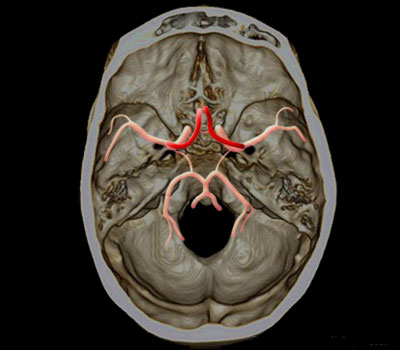

Artères cérébrales antérieure

Territoire de l’artère cérébrale antérieure